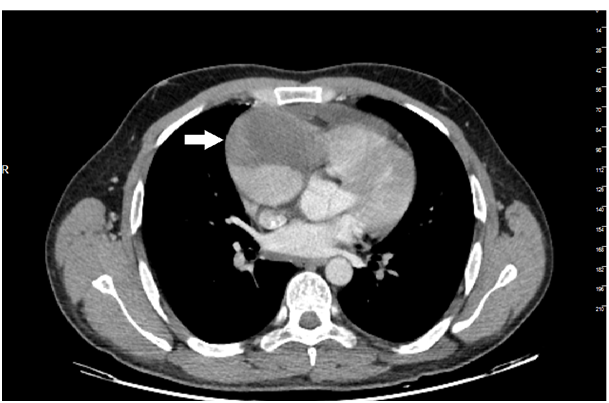

27years old male patient admitted to our outpatient clinic with progressive, pleuritic chestpain unrelated to exertion for a month with no significant medical history. The patient was diagnosed with acute pericarditis at an center and receiving ibuprofen and colchium treatment for three weeks. There was no pathological finding on cardiacaus cultation, blood pressure was 110/80mmHg, heart rate was 110bpm. Electrocardiography showed sinustachicardia and minimal ST segment elevation in all leads. There was a slight cardiomegaly in chest X-ray (Figure 1). Cardiac markers and inflammatory marker were elevated; troponin-I 1112ng/L (0-100), CK748 U/L (0-190), CK-MB 95 U/L(3-25), ESR 65, CRP 75 was detected. Transthorasic echocardiography revealed a 45x60 mm of cavitary mass compressing the right atrial free wall along with pericardial effusion (Figure 2); which was the only location of pericardial effusion in his previous examination a month ago. The patient was admitted to CCU. An aneursym 100x70x60mm in diameter, originating from right coronary artery extending to right atriallateral wall border and compressing externally, which contains thrombus material in its cavity was detected in cardiac computed tomography (CT) (Figure 3). Coronary angiography revealed a giant aneurysm communicated with RCA (Figure 4) without any abnormalty on left coronary arteries. The patient was given to emergency surgery because of the risk of pericardial tamponade. Aneurysmectomy was done and the remained cavity was closed primarily. Pathological examination was reported as polymorpho nuclear leukocyte and mononuclear inflammatory cell infiltration without elastic fibers and a pseudoaneursym of the coronary artery. The patient was discharged without any complication.

Figure 1 Cardiomegaly in chest X-Ray.